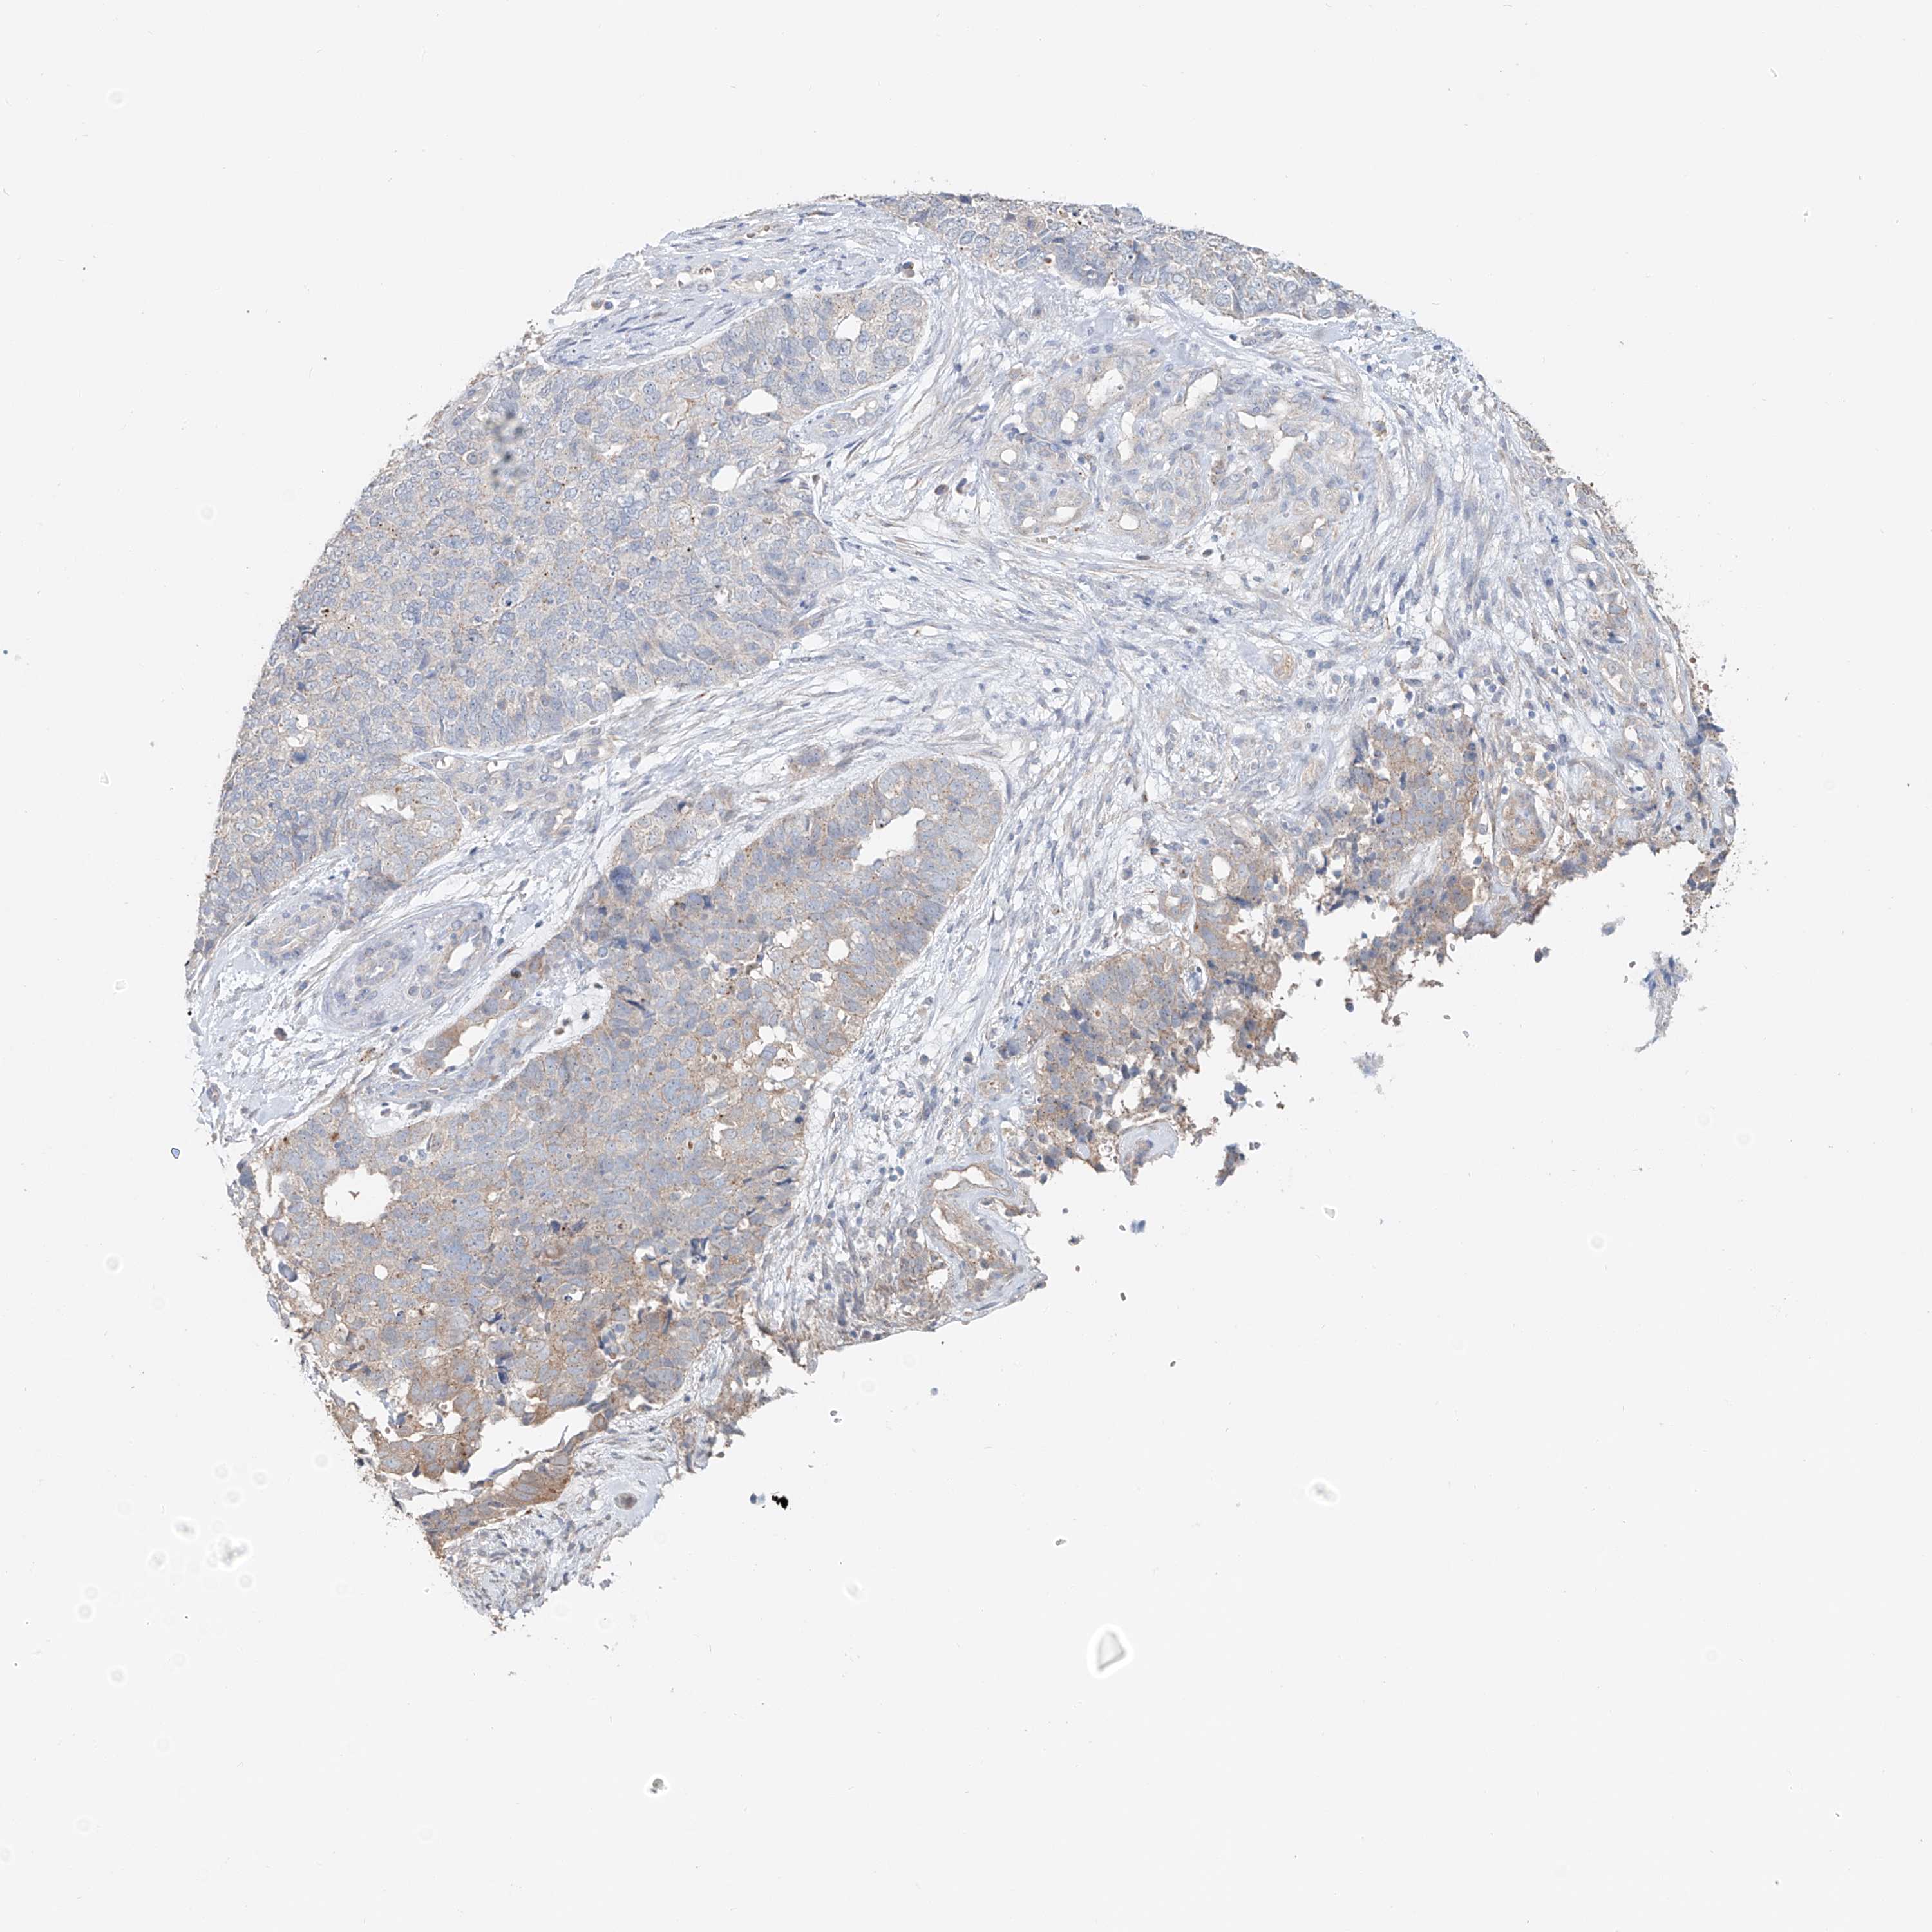

CERVICAL CANCER - Protein expressioni

A mouse-over function shows sample information and annotation data. Click on an image to view it in a full screen mode. Samples can be filtered based on level of antibody staining by selecting one or several of the following categories: high, medium, low and not detected. The assay and annotation is described here.

Note that samples used for immunohistochemistry by the Human Protein Atlas do not correspond to samples in the TCGA dataset.

Antibody stainingi

Antibody staining in the annotated cell types in the current human tissue is reported as not detected, low, medium, or high, based on conventional immunohistochemistry profiling in selected tissues. This score is based on the combination of the staining intensity and fraction of stained cells.

Each image is clickable and will lead to virtual microscopy that enables deeper exploration of all samples and also displays staining intensity scores, fraction scores and subcellular localization as well as patient and tissue information for each sample.

Antibody HPA014933

Staining

High

Medium

Low

Not detected

Intensity

Strong

Moderate

Weak

Negative

Quantity

>75%

75%-25%

<25%

None

Location

Nuclear

Cytoplasmic/membranous

Cytoplasmic/membranous,nuclear

Squamous cell carcinoma, NOS

Adenocarcinoma, NOS